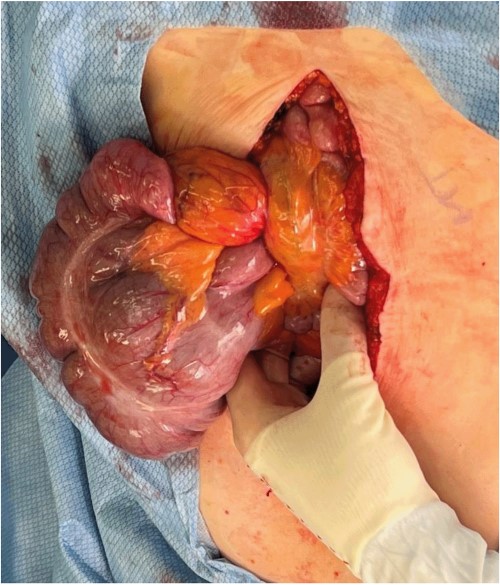

A midline laparotomy was made. A midgut volvulus was encountered immediately upon entering the abdomen and was subsequently reduced from the left upper quadrant. The cecal and ascending colon volvulus had a 540 degree rotation with viable tissues on reduction; however, the ascending colon had a narrow, non-adherent mesentery allowing a point of volvulus while also folding over a Ladd’s band attached to the right lower quadrant of the abdomen. The bowel was then run, and it was confirmed that there was no present ligament of Treitz and that the patient did indeed have congenital malrotation (Fig. 2). There was no retroperitoneal component of duodenum, and it was completely without fixation to other structures. Ladd’s bands were encountered and lysed (Fig. 3).

Identification of Ladd’s bands and lack of retroperitoneal course of the duodenum after detorsion of the midgut volvulus.